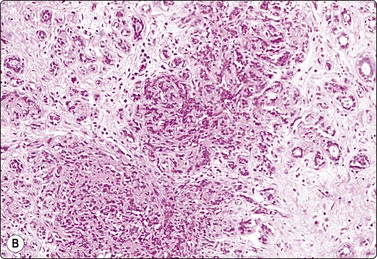

FNB and CNB in the follow-up of breast cancer

The FNB diagnosis of local recurrence of breast cancer is generally straightforward, involving a distinction between cancer and suture granuloma, fat necrosis and scarring.16-19 However, reactive atypia in reparative granulation tissue, in fat necrosis or in seroma cavities can cause diagnostic problems, and radiation-induced atypia in benign glandular epithelium can be misinterpreted as recurrent malignancy (Fig. 7.1). CNB can also be used; however, fat necrosis may be misinterpreted as invasive carcinoma on core, leading to a false-positive diagnosis of malignancy.20 Sampling error by core biopsy should always be considered in cases where the suspicion of recurrence is high.

Fig. 7.1 Radiation-induced atypia

(A) The epithelial cells in this irregular cluster show considerable nuclear enlargement, pleomorphism and hyperchromasia, but also some degenerative changes such as loss of nuclear structure (MGG, HP); (B) Corresponding tissue section (H&E, IP).